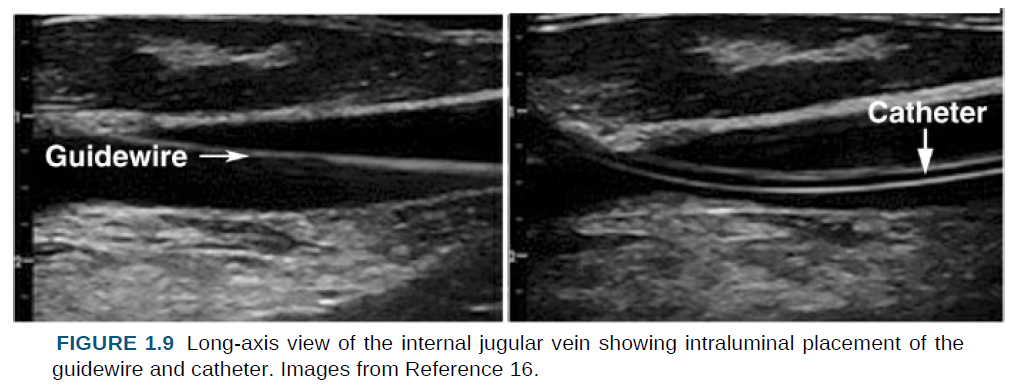

장축 보기는 삽관 중 탐침 바늘, 가이드와이어, 카테터를 시각화할 수 있다는 장점이 있다.

반면 가이드와이어와 카테터가 혈관 내강에 위치했음을 확인하는 데에는 장축 보기가 선호된다.

이 확인 과정은 먼저, 그림 1.9의 왼쪽에 제시된 것처럼, 가이드와이어가 혈관 내강으로 전진되었음을 확인하는 것에서 시작한다.

그다음 카테터를 가이드와이어 위로 전진시키고, 그림 1.9의 오른쪽에 제시된 것처럼, 카테터가 혈관 내강에 위치했음을 최종적으로 확인한다.